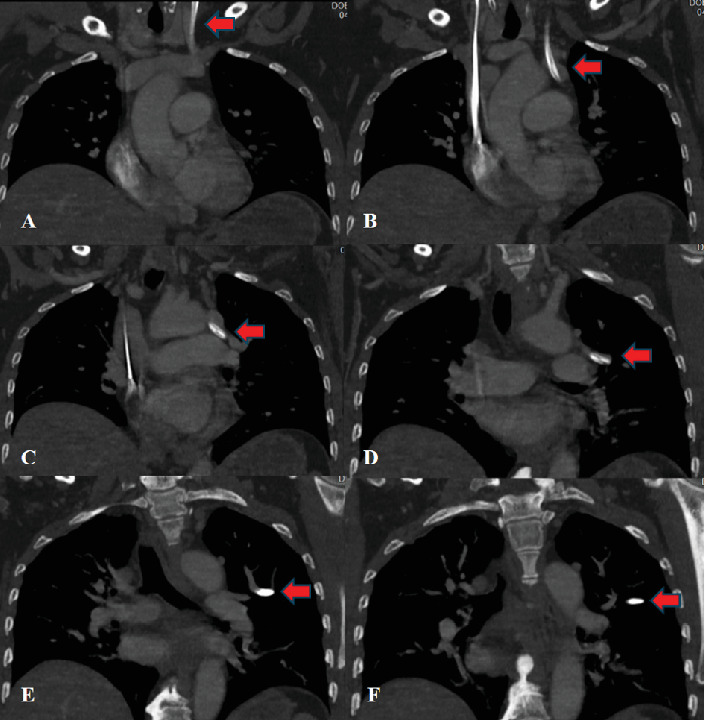

Background: Partial anomalous pulmonary venous connections are embryologic defects in which the normal connection between the pulmonary veins and left atrium is disrupted. These rare anomalies are often asymptomatic and identified incidentally. The most common variant is a connection between the left upper pulmonary veins and the left innominate vein. Although typically asymptomatic, these variants are important to be aware of, particularly when performing procedures involving the venous anatomy. Case Presentation: We present the case of a 52-year-old female with a previous history of colon cancer who underwent right hemicolectomy and presented to the hospital due to severe dehydration secondary to profuse nausea, vomiting, and diarrhea. She developed an acute kidney injury with electrolyte derangement and metabolic acidosis requiring initiation of hemodialysis. Due to her preexisting right internal jugular port access, the decision was made to proceed with left internal jugular dialysis catheter access. Central venous access was performed in standard fashion. There was venous-appearing blood return at the time of needle access and subsequent dilations. However, at the time of catheter advancement, there was noted return of bright red blood and resistance to advancement, concerning for possible arterial cannulation. Concerning arterial placement, an arterial blood gas (ABG) test and chest x-ray were performed; however, the transducer waveforms were not consistent with this. Computed tomography angiography obtained revealed left internal jugular venous access with catheter extension into an anomalous pulmonary vein within the left upper lobe. The patient was taken to the angiography suite and under fluoroscopy guidance had new left internal jugular catheter access with the catheter terminating successfully in the superior vena cava. She underwent successful dialysis and was subsequently discharged on postprocedure Day 8. Conclusions: Central line placement is a commonly performed procedure in hospitals. There are steps that have been developed to limit complications for this procedure, including ultrasound guidance, visualization of venous blood, and confirmatory imaging prior to use. This is a case in which arterial-appearing blood, paO2, and chest x-ray were concerning for incorrect placement, but additional imaging revealed accurate access with anomalous anatomy. Overall, the case of central line placement in anomalous pulmonary venous connections is rare but needs consideration when the clinical scenario is appropriate.